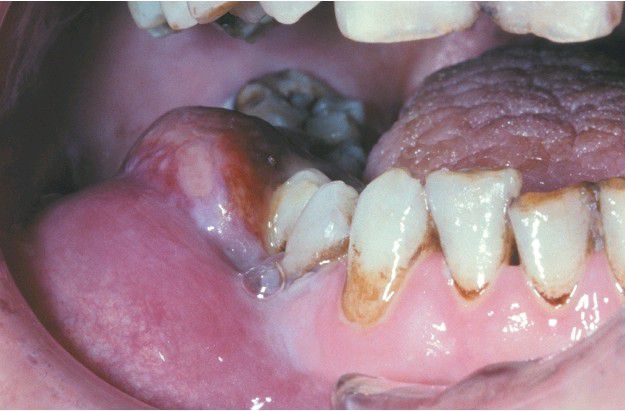

Erythematous and ulcerated soft tissue enlargement of the posterior mandibular gingiva and mucobuccal fold on the right side.